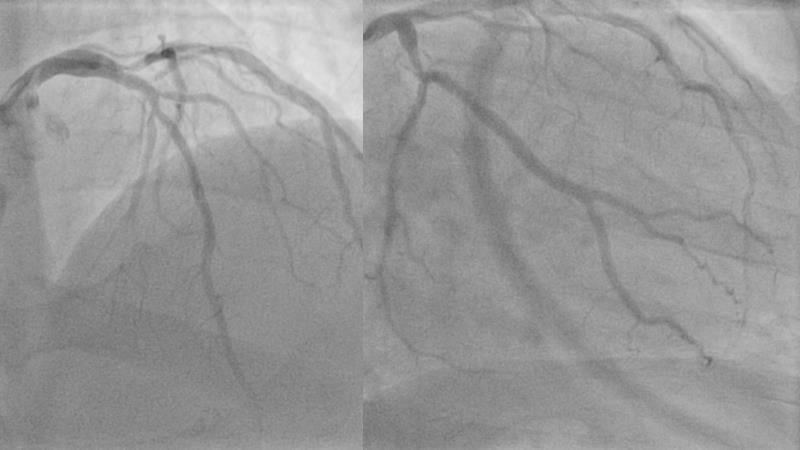

Join this session to explore the advantages of a fully optical approach in optimizing percutaneous coronary intervention (PCI) with the OptoWire III physiology wire and Nipro HF-OCT catheter. Through a practical case, you'll discover the significance of coronary physiology and intravascular imaging in bifurcation PCI and gain insights into how the performance and accuracy of the OptoWire III physiology wire can facilitate fast and reliable decision-making, particularly in side branch jailing scenarios.

- To review, through a practical case, the value of coronary physiology and intravascular imaging in bifurcation PCI